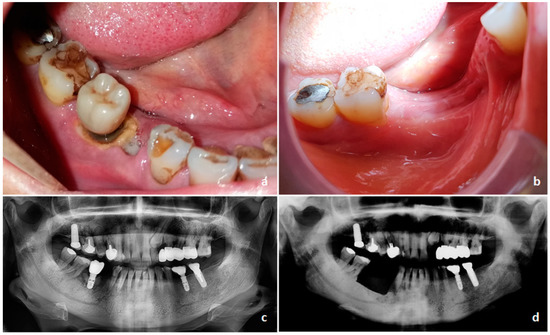

- Ruggiero, S.L.; Dodson, T.B.; Fantasia, J.; Goodday, R.; Aghaloo, T.; Mehrotra, B.; O’Ryan, F. American Association of Oral and Maxillofacial Surgeons Position Paper on Medication-Related Osteonecrosis of the Jaw—2014 Update. J. Oral Maxillofac. Surg. 2014, 72, 1938–1956. [Google Scholar] [CrossRef]

- Khan, A.A.; Morrison, A.; Hanley, D.A.; Felsenberg, D.; McCauley, L.K.; O’Ryan, F.; Reid, I.R.; Ruggiero, S.L.; Taguchi, A.; Tetradis, S.; et al. Diagnosis and Management of Osteonecrosis of the Jaw: A Systematic Review and International Consensus. J. Bone Miner. Res. 2015, 30, 3–23. [Google Scholar] [CrossRef] [PubMed]

- Fedele, S.; Bedogni, G.; Scoletta, M.; Favia, G.; Colella, G.; Agrillo, A.; Bettini, G.; Di Fede, O.; Oteri, G.; Fusco, V.; et al. Up to a quarter of patients with osteonecrosis of the jaw associated with antiresorptive agents remain undiagnosed. Br. J. Oral Maxillofac. Surg. 2015, 53, 13–17. [Google Scholar] [CrossRef] [PubMed]

- Khan, A.; Morrison, A.; Cheung, A.; Hashem, W.; Compston, J. Osteonecrosis of the jaw (ONJ): Diagnosis and management in 2015. Osteoporos. Int. 2016, 27, 853–859. [Google Scholar] [CrossRef] [PubMed]

- Fliefel, R.; Tröltzsch, M.; Kühnisch, J.; Ehrenfeld, M.; Otto, S. Treatment strategies and outcomes of bisphosphonate-related osteonecrosis of the jaw (BRONJ) with characterization of patients: A systematic review. Int. J. Oral Maxillofac. Surg. 2015, 44, 568–585. [Google Scholar] [CrossRef] [PubMed]

- Otto, S.; Tröltzsch, M.; Jambrovic, V.; Panya, S.; Probst, F.; Ristow, O.; Ehrenfeld, M.; Pautke, C. Tooth extraction in patients receiving oral or intravenous bisphosphonate administration: A trigger for BRONJ development? J. Cranio-Maxillofacial Surg. 2015, 43, 847–854. [Google Scholar] [CrossRef]